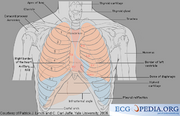

| 13:35, 25 September 2007 | Torso.png (file) |  |

87 KB | Vdbilt | Torso Schematic | 1 |